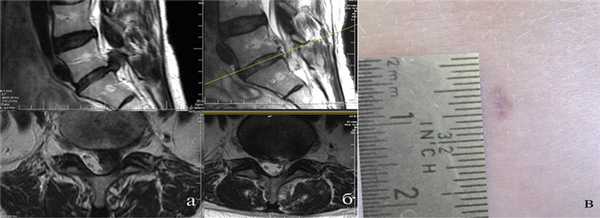

Больной К., 56 лет, занимается среднетяжелым физическим трудом, работает в энергетической компании. Предъявляет жалобы на боль в поясничном отделе позвоночника и в левой ноге по задней поверхности бедра и голени. Указанные жалобы беспокоят в течение 3 мес. Лечился консервативно в поликлинике у невролога без видимого эффекта. Клинически: со стороны черепно-мозговых нервов без патологии, сухожильные, периостальные рефлексы на руках и ногах симметричные, парезов и нарушений чувствительности нет, симптомы натяжения слева с 30°. МРТ пояснично-крестцового отдела позвоночника показала наличие парамедианной грыжи диска L5—S1 слева (рис. 5, а). На 2-е сутки госпитализации выполнена операция — интерламинарная ПЭД с интраоперационным навигационным контролем. Продолжительность операции 65 мин, кровопотеря минимальная, без особенностей, удалено около 2 мл измененной ткани межпозвонкового диска. В послеоперационном периоде отмечен полный регресс корешкового болевого синдрома. Жалобы на умеренные боли в области операции, купированные 4-кратным внутримышечным введением кетопрофена. Выписан на 1-е сутки после операции. В послеоперационном периоде рецидива болей не отмечалось, по данным контрольной МРТ, рецидива грыжи межпозвонкового диска нет (см. рис. 5, б). Послеоперационный рубец имеет длину менее 0,5 см (см. рис. 5, в).

Рис. 5. МРТ поясничного отдела позвоночника пациента К. а — до операции; б — через 1 мес после операции; в — рубец на месте операционной раны после перкутанной эндоскопической дискэктомии.